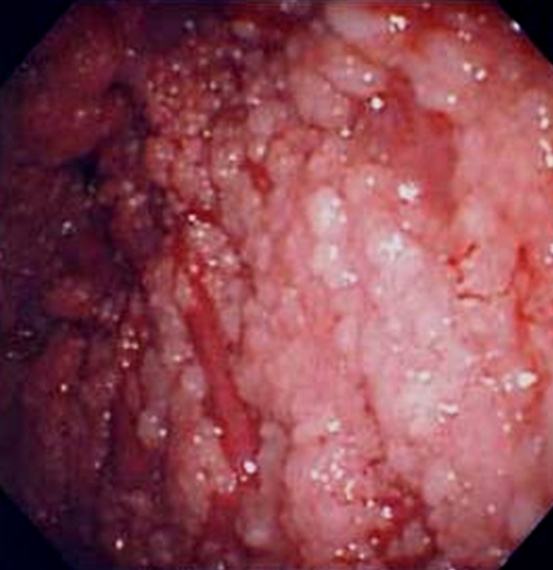

T1a期(IMIG分類)の胸膜中皮腫の胸腔鏡所見

壁側胸膜に顆粒状の腫瘍を認める。